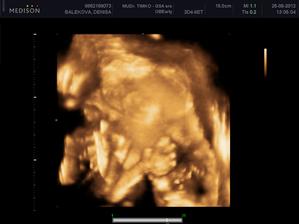

Nas anjelik Alex

Zatial este schovany v brusku ale uz coskoro sa z neho potesime aj nazivo 🙂) Lubime nasho Alexa uz od sameho zaciatku 🙂